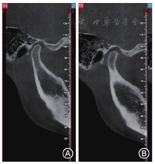

畸形)。TMD好发于青壮年,女性多见,以20 ~ 30岁患病率最高,发病率达28% ~ 88%。TMD分为功能紊乱病、结构紊乱病、炎性疾病和骨关节病四大类。临床上最常见的疾病类型往往与颞下颌关节盘相关,也就是结构紊乱。颞下颌关节盘根据其位置可分为正常、可复性关节盘前移位、不可复性关节盘前移位(图1)。TMD的"三大"主要症状是下颌运动异常、关节区疼痛、弹响与杂音等,此外还有"三小"症状,即部分患者伴有头痛、耳部症状(耳鸣)、心理疾病[1,2,3]。